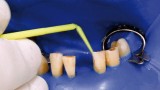

Jedną z popularniejszych metod stabilizacji zębów rozchwianych jest ich szynowanie. Metoda ta, wspierająca inne metody leczenia, jest powszechnie stosowana. Jednym z najnowocześniejszych materiałów wykorzystywanych w stomatologii do szynowania zębów jest taśma poliaramidowa. W opisanym przypadku autorzy pracy przedstawiają sposób uproszczenia całej procedury i ograniczenia ryzyka popełnienia błędu, szczególnie w sytuacji całkowitej utraty zęba. Uzyskano to dzięki zastosowaniu indeksu wykonanego z przezroczystego silikonu.

One of the more popular methods of stabilising loose teeth is to splint them. This method, aiding other methods of treatment, is generally used. One of the most modern materials used in dentistry for splinting teeth, is polyamide tape. In the case described the authors show how to simplify the whole procedure and limit the risk of making a mistake, particularly in the situation of total loss of one tooth. This was achieved thanks to the use of an index made out of transparent silicone.